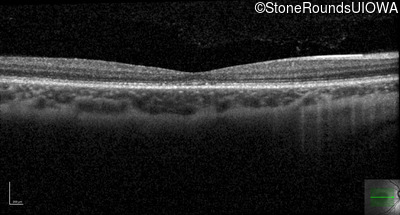

Optical Coherence Tomography - Right - 20/32

Exemplar / OCT Stack

OCT Stack

Optical Coherence Tomography - Left - 20/32 -1